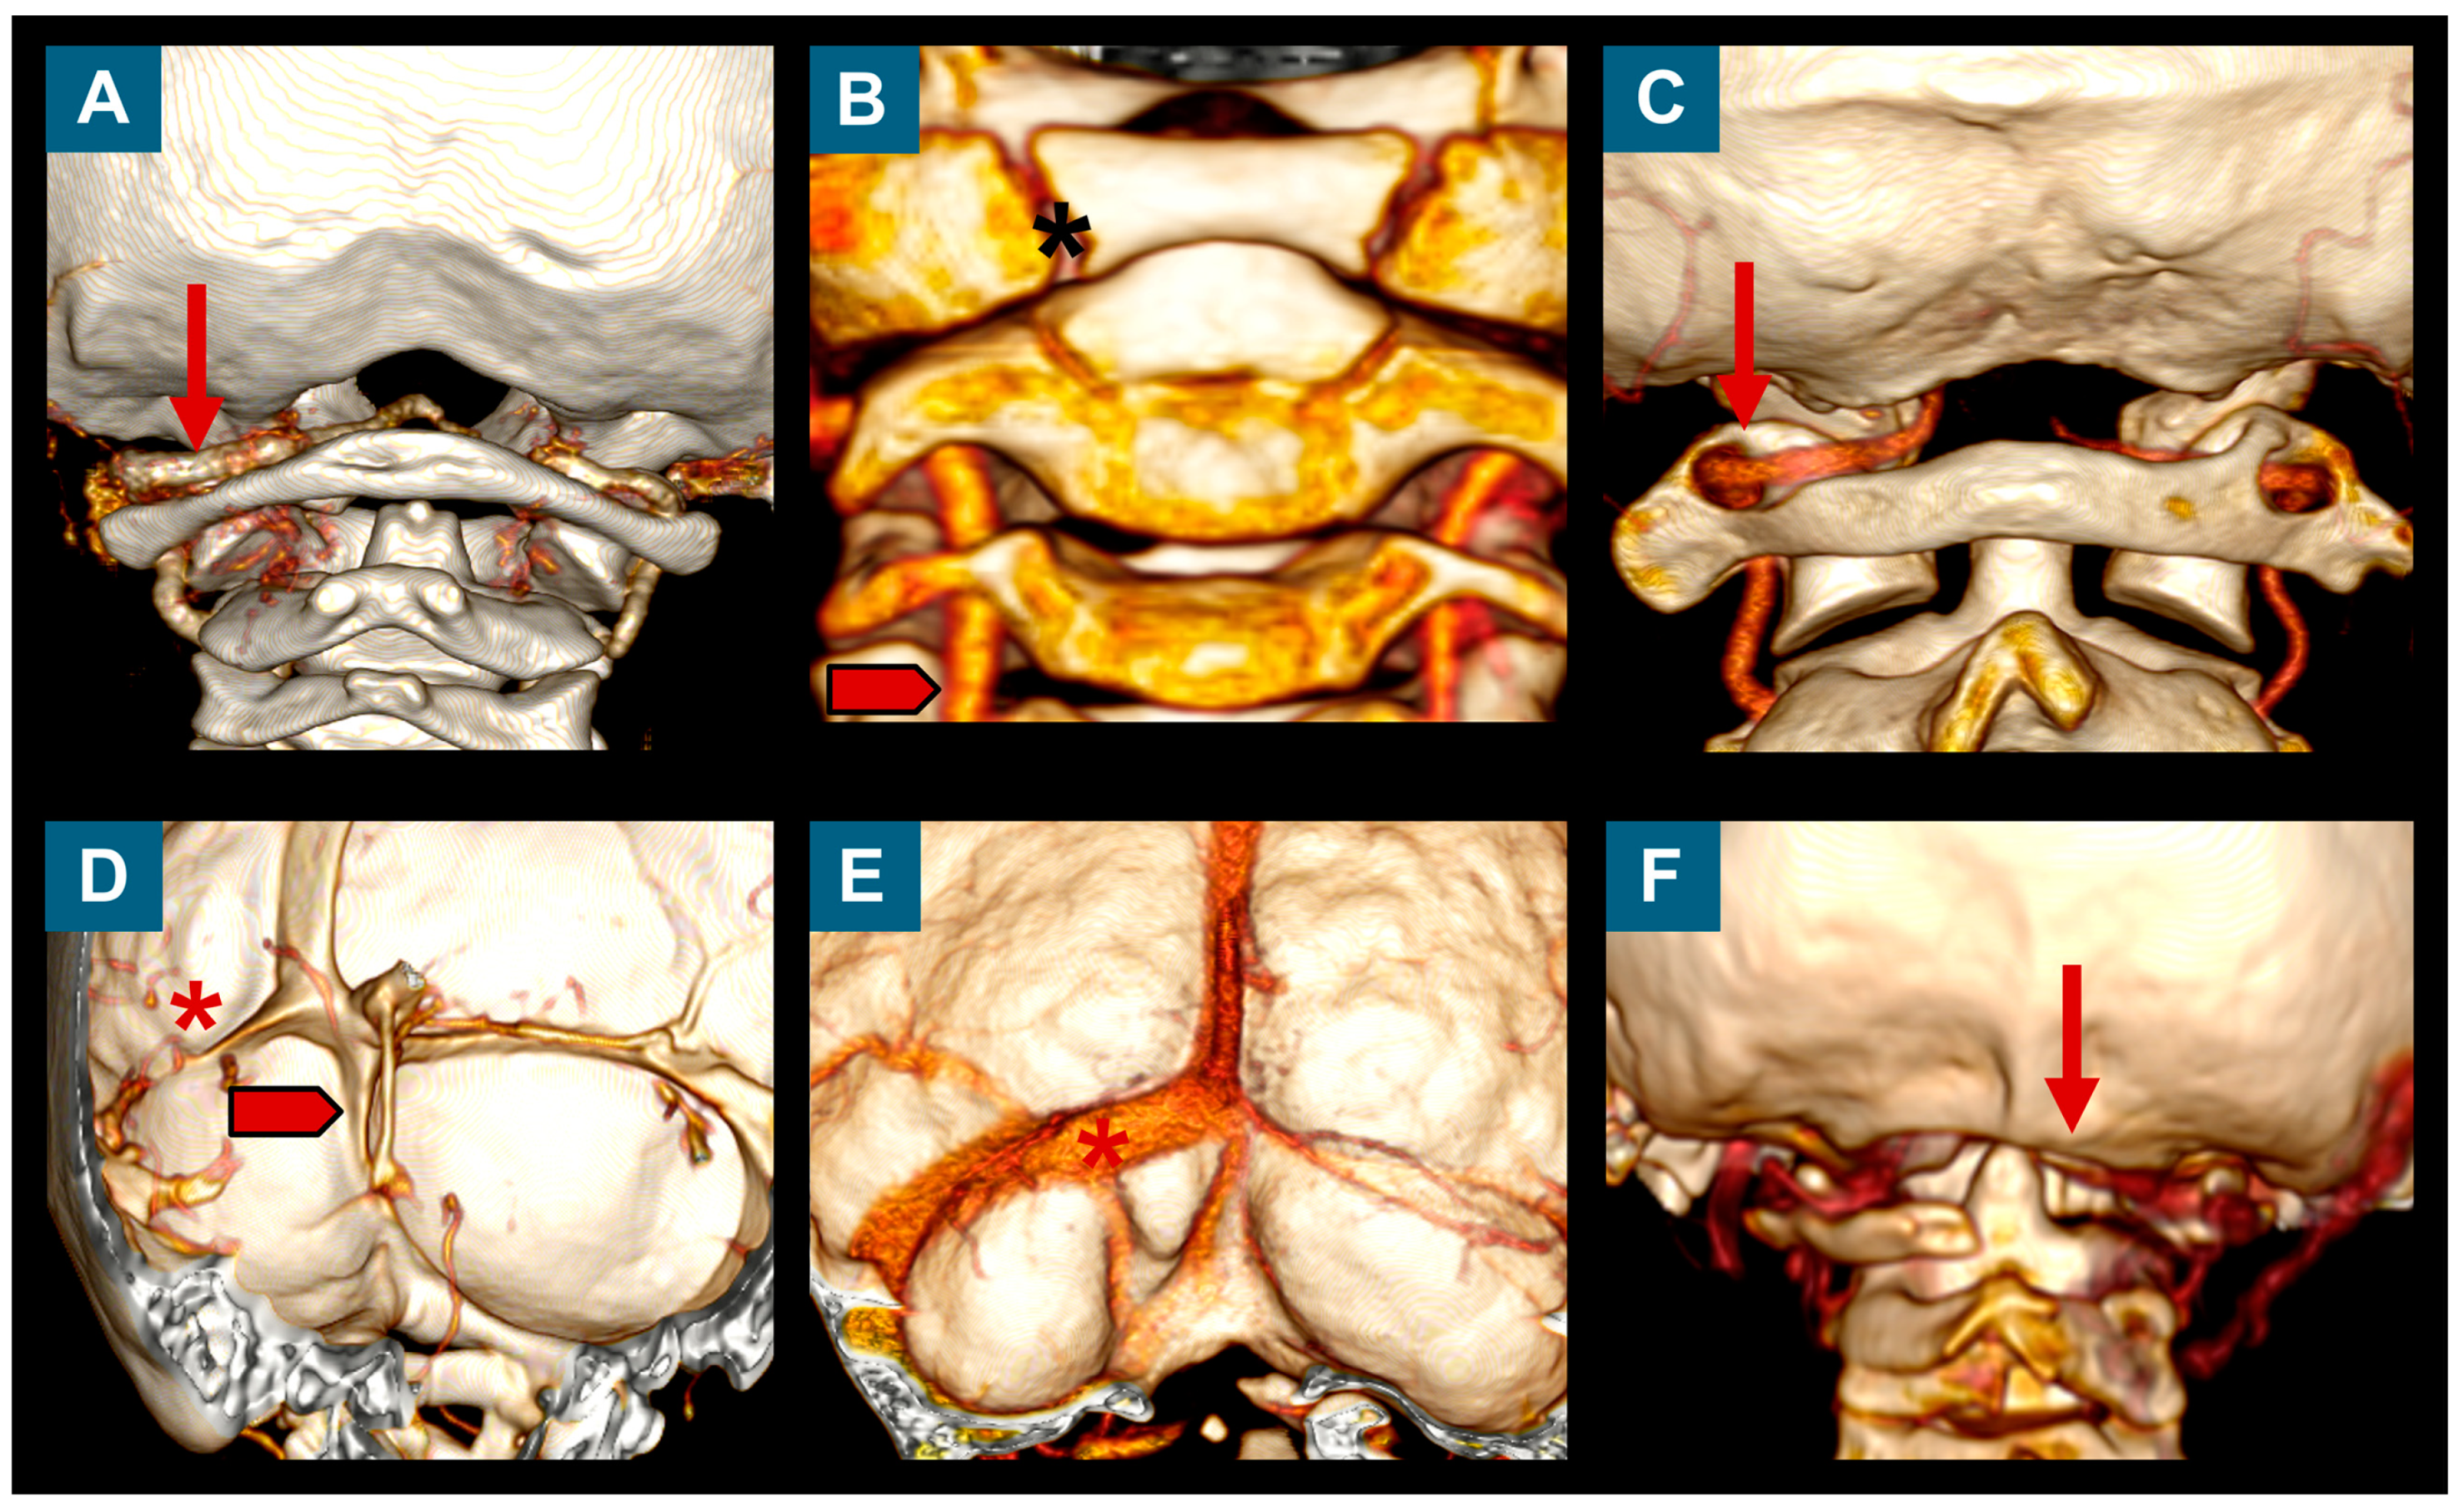

3.5. Neuroimaging Findings before and after Surgery